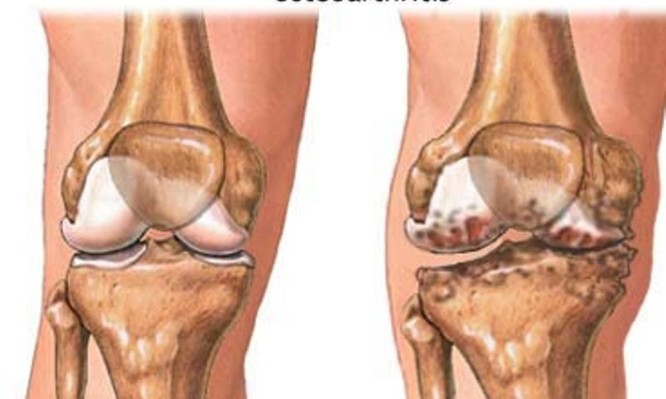

«Πρόκειται για μια εκφυλιστική ασθένεια των αρθρώσεων που εξελίσσεται καθώς ο χόνδρος με την πάροδο του χρόνου φθείρεται, ή που ξεκινά ως αντίδραση στο στρες στην οποία υποβάλλεται το οστό μετά από τραυματισμό του. Απ’ αυτή υποφέρουν εκατομμύρια άνθρωποι παγκοσμίως και κατατάσσεται μεταξύ των πιο συχνών χρόνιων νόσων. Εκτός από οίδημα και απώλεια χόνδρου, οι άνθρωποι με οστεοαρθρίτιδα μπορεί επίσης να βιώνουν δυσκαμψία και πόνο» συμπληρώνει.

Τα ευρήματα από τις περισσότερες μελέτες συγκλίνουν στο συμπέρασμα ότι η ύπαρξη οστεοαρθρίτιδας αποτελεί παράγοντα κινδύνου όταν υφίσταται στο γόνατο ή στο ισχίο, αλλά είναι αντικρουόμενα όταν εντοπίζεται στο χέρι. Επιστήμονες από το Πανεπιστήμιο της Οτάβα και του Τορόντο στον Καναδά, ερεύνησαν το θέμα σε 18.490 συμμετέχοντες.

Διαπιστώθηκε ότι τα άτομα με οστεοαρθρίτιδα στο γόνατο ή στο ισχίο, αλλά όχι στο χέρι, ήταν σημαντικά πιο πιθανό να υποστούν καρδιαγγειακό επεισόδιο. Συγκεκριμένα, ο κίνδυνος ήταν κατά 13% υψηλότερος στους ασθενείς που είχαν οστεοαρθρίτιδα σε τουλάχιστον δύο γοφούς ή/και γόνατα σε σύγκριση με εκείνους που δεν είχαν οστεοαρθρίτιδα, και κατά 22% όταν η νόσος εντοπιζόταν σε τρεις ή περισσότερες αρθρώσεις (ισχία ή γόνατα).